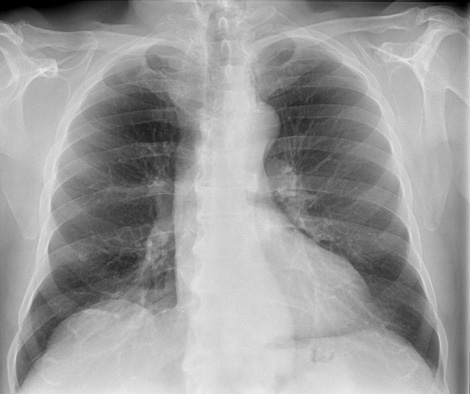

Excellent images

UNIQUE 2 image processing

Excellent images

UNIQUE 2 image processing